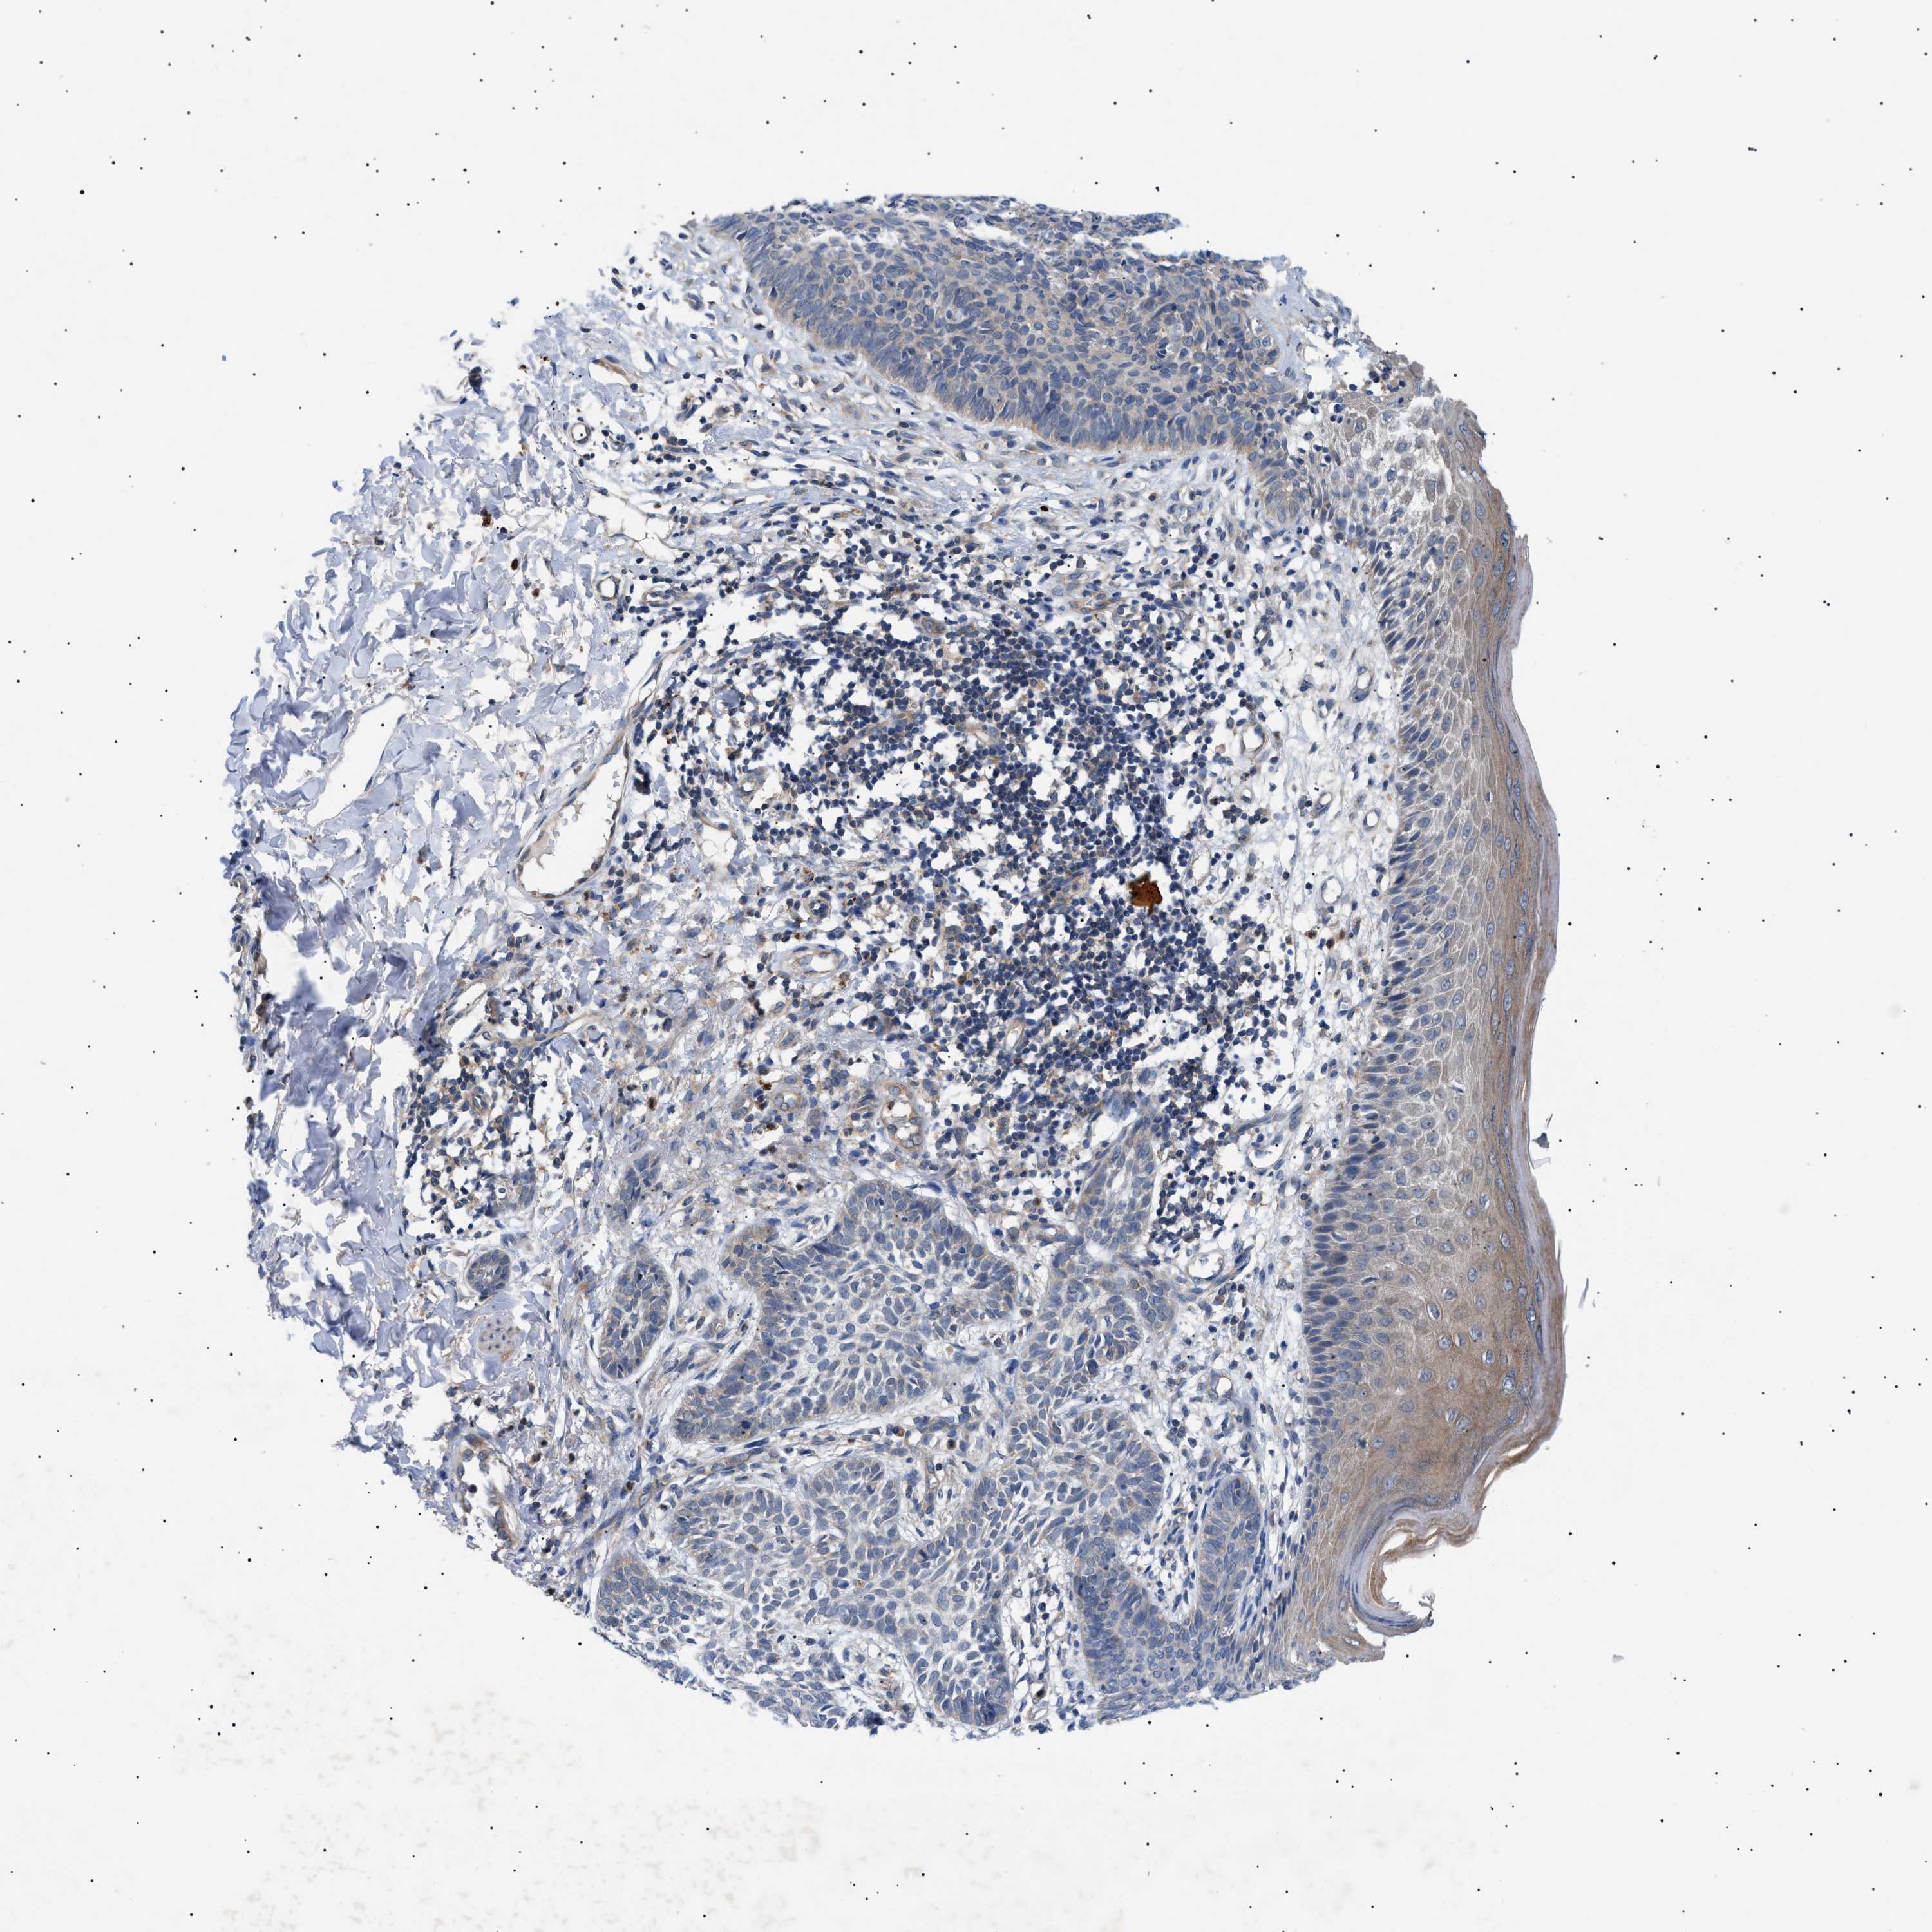

CANCER SKIN CANCER Show tissue menu

Basal cell and squamous cell cancer

SKIN CANCER - Protein expressioni

A mouse-over function shows sample information and annotation data. Click on an image to view it in a full screen mode. Samples can be filtered based on level of antibody staining by selecting one or several of the following categories: high, medium, low and not detected. The assay and annotation is described here.

Each image is clickable and will lead to virtual microscopy that enables deeper exploration of all samples and also displays staining intensity scores, fraction scores and subcellular localization as well as patient and tissue information for each sample.

Antibody HPA015257

Antibody CAB010302

Staining

High

Medium

Low

Not detected

Intensity

Strong

Moderate

Weak

Negative

Quantity

>75%

75%-25%

<25%

None

Location

Nuclear

Cytoplasmic/membranous

Cytoplasmic/membranous,nuclear

Squamous cell carcinoma in situ, NOS

Squamous cell carcinoma, NOS

Squamous cell carcinoma, metastatic, NOS

Basal cell carcinoma

Adnexal tumor, benign